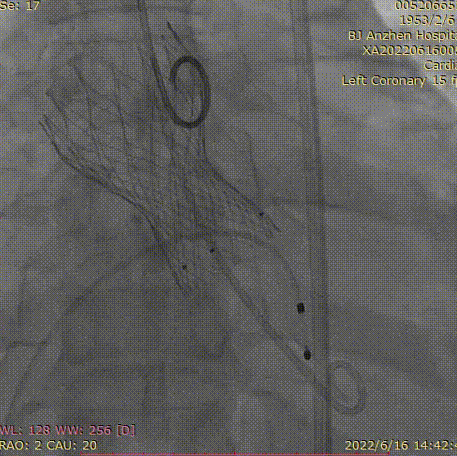

冠状动脉造影

13点35分,准备工作就绪,在宋光远教授带领下,手术团队迅速而有条不紊的完成股动静脉穿刺、置入鞘管、安置临时起搏电极、主动脉窦造影、导丝跨瓣、冠脉造影等一系列操作。接下来就要对患者狭窄的主动脉瓣进行球囊扩张,这是手术中风险很高的步骤,因球囊扩张时需要快速起搏心室,而患者心功能储备差,短暂的起搏也可能造成循环崩溃;所以需要整个手术团队密切配合,以确保万无一失。